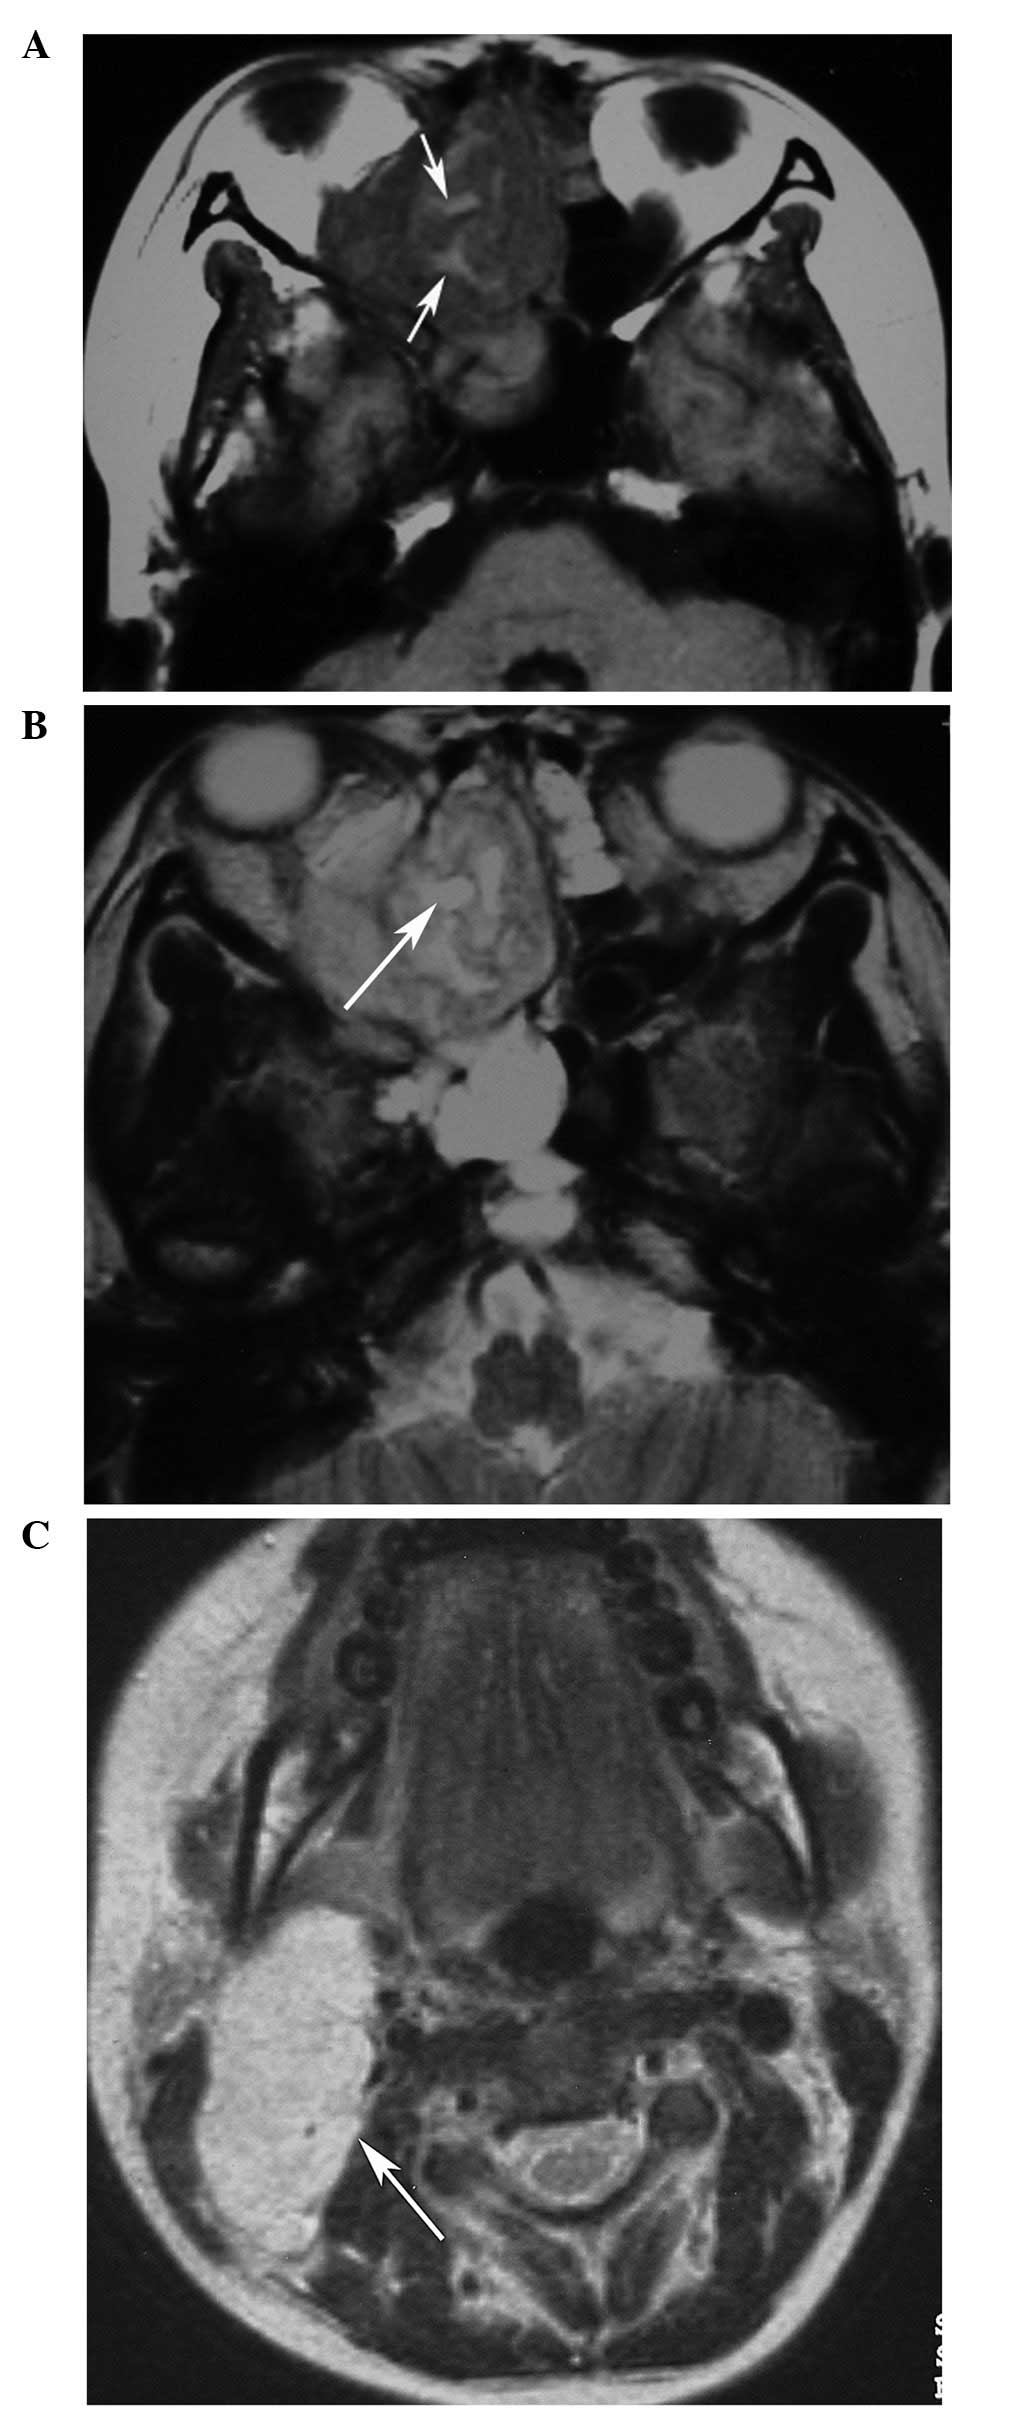

Parameningeal Head And Neck Rhabdomyosarcoma. A Axial T1-W MR Image In

Computed Tomography And Magnetic Resonance Imaging Observations Of

www.spandidos-publications.com

www.spandidos-publications.com

rhabdomyosarcoma computed tomography magnetic imaging observations resonance neck head figure ol

Computed Tomography And Magnetic Resonance Imaging Observations Of

www.spandidos-publications.com

www.spandidos-publications.com

rhabdomyosarcoma neck head embryonal axial resonance magnetic observations imaging computed tomography ol figure

Computed Tomography And Magnetic Resonance Imaging Observations Of

www.spandidos-publications.com

www.spandidos-publications.com

rhabdomyosarcoma tomography magnetic imaging computed observations resonance neck head ol figure publications spandidos